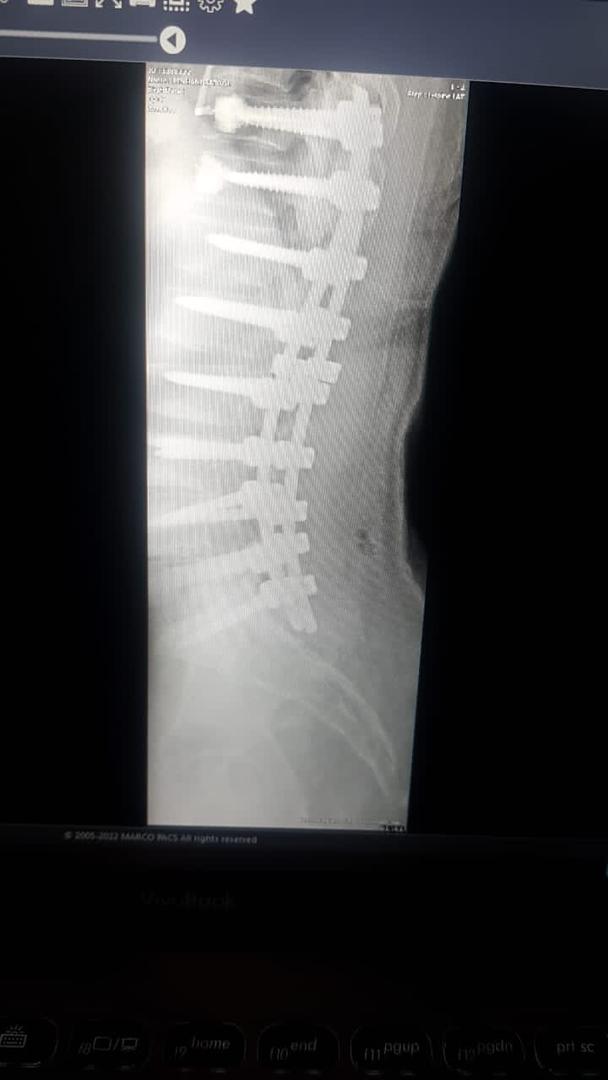

دکتر احمد جباری در توضیح عمل دوم گفت : انحراف در ستون فقرات یا اسکولیوزتوراکولومبار یعنی انحراف در وسط و پایین کمراست  که مهره ها کاملا حول محور افقی و عمودی ستون فقرات یعنی در هر دو محور پیچیده می شود و چون  اصلاح بسیار سخت و عمل ظرافت بالایی دارد جزء عمل های بسیار پیچیده ستون فقرات می باشد که شکرخدا توانستیم بدون هیچ عارضه ای در این عمل 9 مهره را پلاتین گذاری کنیم ،انحراف به وجود آمده را برطرف کرده،دردهای بیمار بهبود پیدا کرده و در نهایت عمل رضایت بخشی انجام شد.